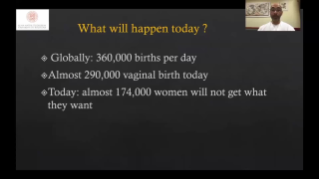

Geburtshilfe